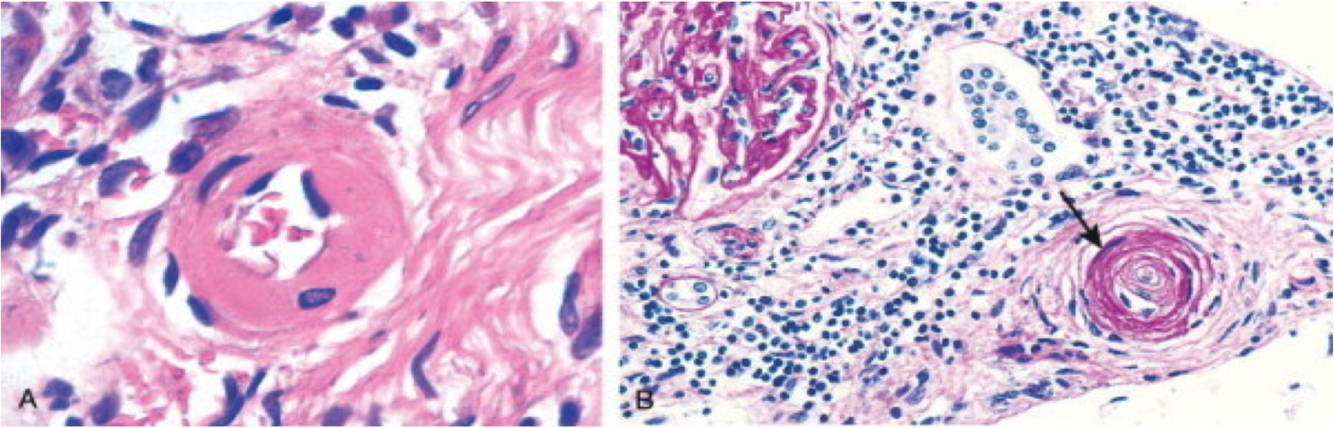

What is shown here?

hyperplastic arteriolosclerosis

seen in malignant HTN

proliferation of smooth muscle cells in the kidney & their media

on gross–hemorrhages seen along edges of kidney